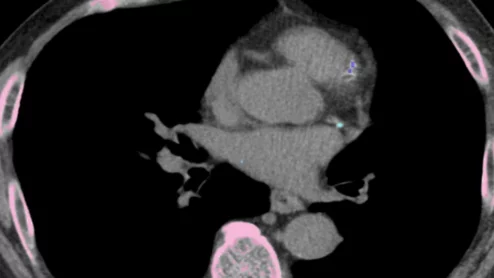

cvi42 | Plaque Circle Cardiovascular Imaging

The use of AI to evaluate plaque buildup in CCTA images has been one of cardiology’s biggest ongoing trends. Implementing this software into existing workflows, however, can be a challenge. An upcoming webinar is focused on providing guidance to hospitals and cardiology practices hoping to learn more about this topic.